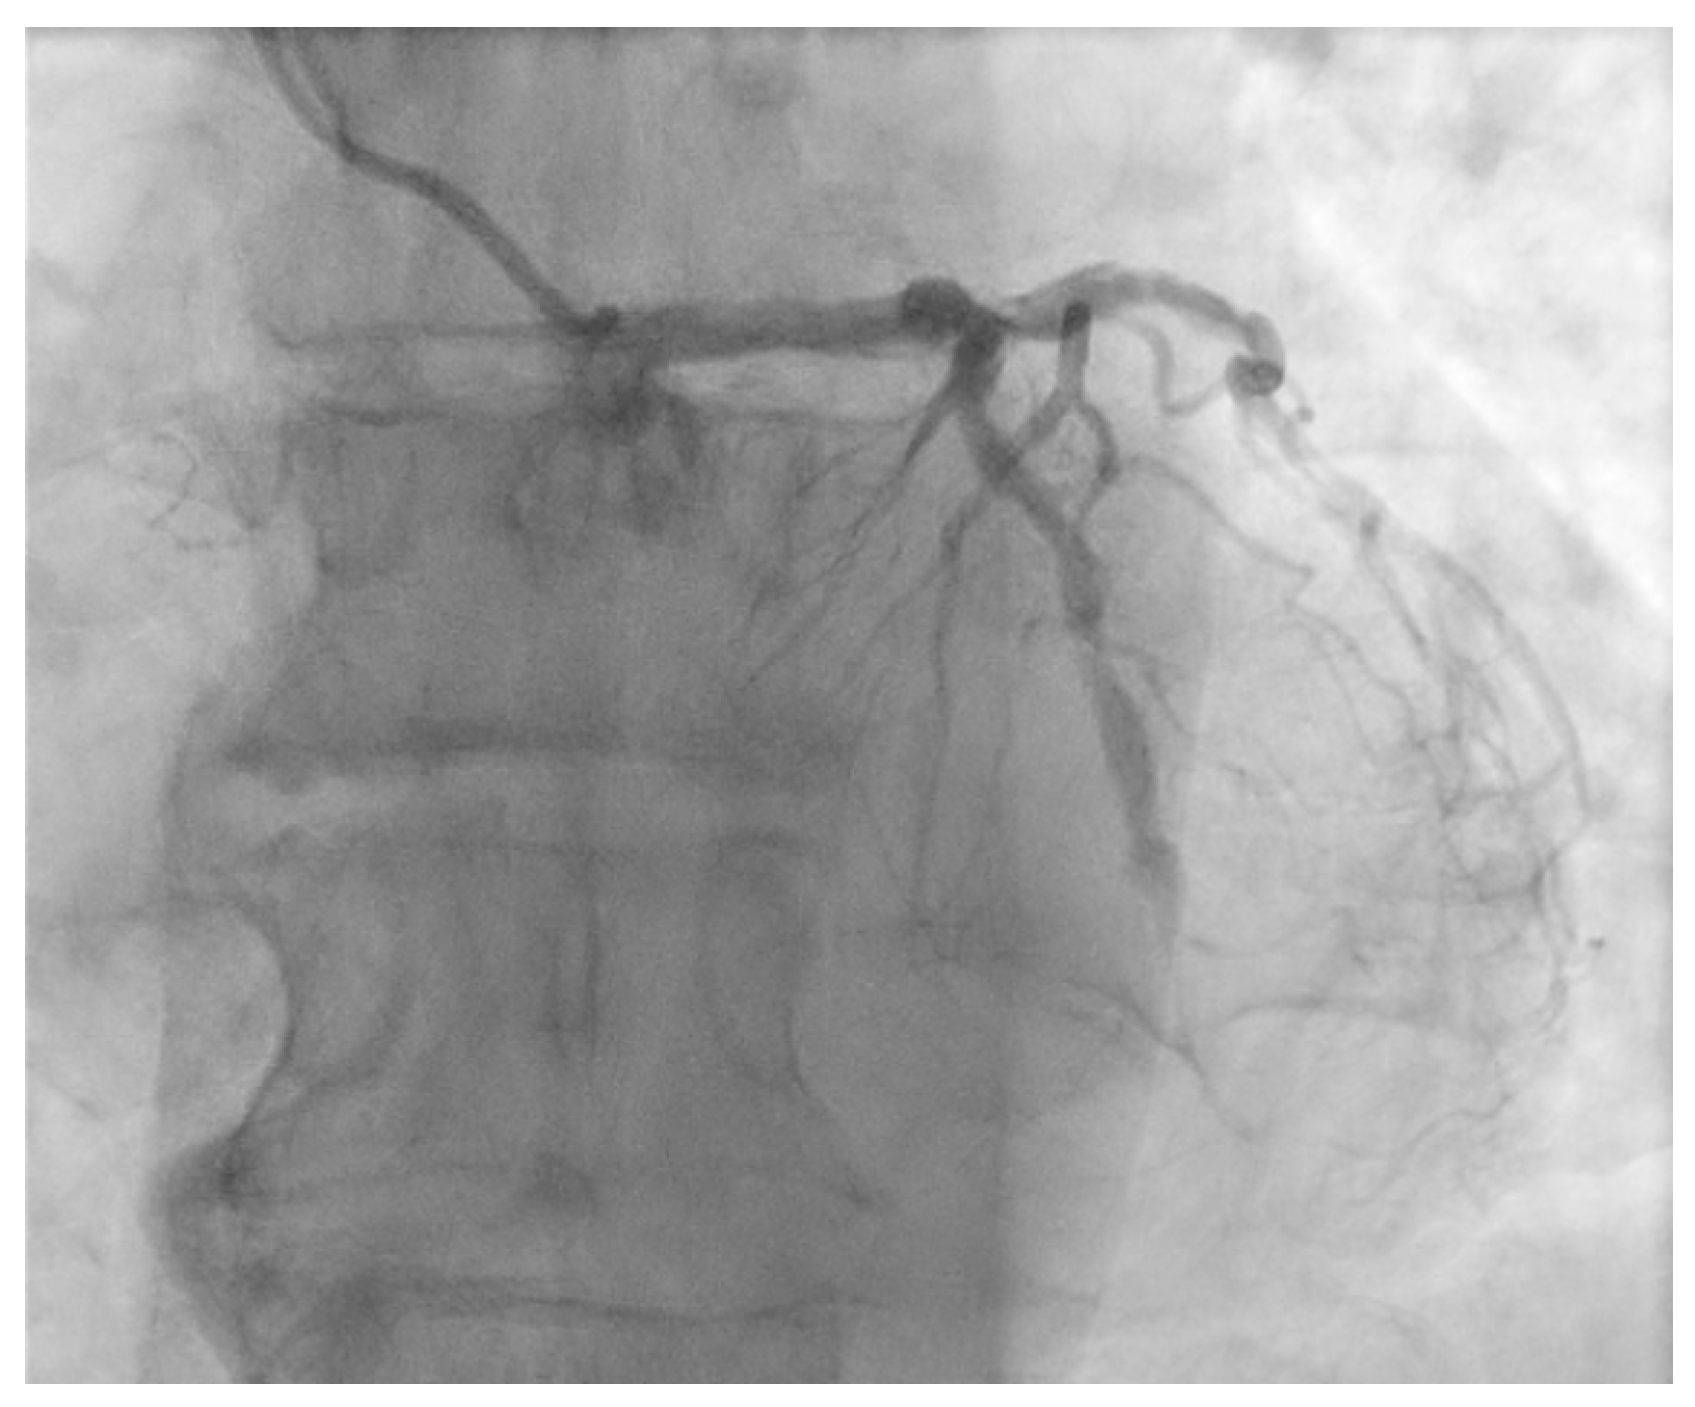

The ostium of left anterior descending artery (LAD) presented a 75% stenotic lesion, with the proximal segment displaying a 90% lesion (Figure 3). The left circumflex artery (LCX) revealed a 75% stenotic lesion of the ostium and tapered disease of its distal segment with areas of ectasic disease, with the ostium of the ramus intermedius (RI/RM) showing a 75% lesion (modified Medina classification 0-1-1-1 [4]) (Figure 4, Figure 5, Figure 6, Figure 7, Figure 8, Figure 9 and Figure 10).

Figure 4.

Left coronary artery—LAD and LCX (LAO caudal). Red arrow and circle—ostium of LAD. Yellow arrow and square—ostium of LCX.